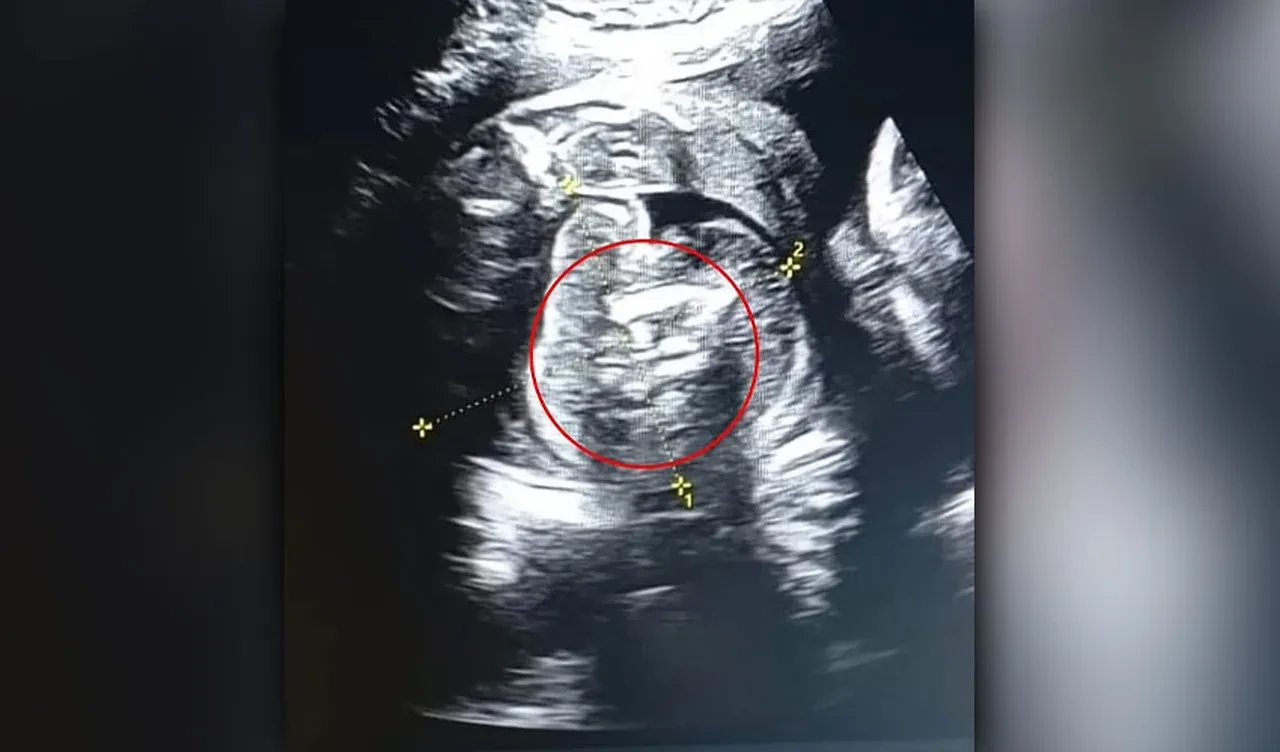

Hindistan'da yaşayan 32 yaşındaki, 35 haftalık hamile bir kadın rutin kontrolü için doktora gitti. Erkek bir bebeğe hamile olan kadının ultrason taraması sırasında doktor, ilginç bir durum olduğunu söyledi. Daha önceki taramaları normal çıkan kadının, doğmamış bebeğinin karnında 'kemik içeren ek bir yapı' keşfedildi. Doktor, iki cismin fetüs olduğunu söylediğinde ise herkes büyük bir şaşkınlık yaşadı.

Uzmanlar, fetüslerin hayatta kalamayacak kadar az gelişmiş olduğunu ifade ettiler. Taramayı gerçekleştiren Dr. Prasad Agarwal, yerel medyaya yaptığı açıklamada , "Bu bebekte çok sıra dışı bir şey fark edecek kadar şanslı ve dikkatliydim; birkaç kemiği ve karnında fetüs benzeri bir yapı bulunduğunu anladım. Bunun normal olmadığını fark ettim. Bu, dünyadaki en nadir vakalardan biri olan 'fetüs içinde fetüs' idi.'' dedi.